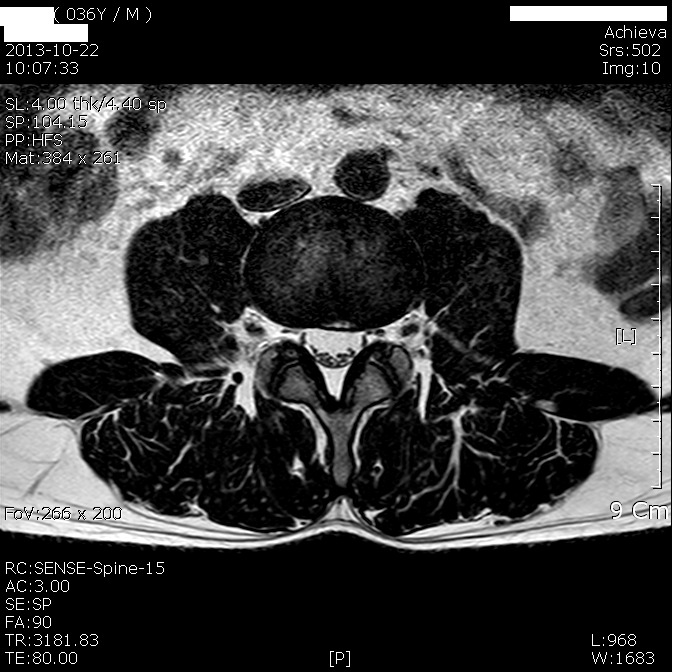

Diffuse annular bulge of C5-6 disc compressing the spinal cord and the corresponding nerve root. Anesthetic options included neuraxial anesthesia above the level of the lumbar lesions or awake fiberoptic intu-bation followed by general anesthesia. ... Access Doc